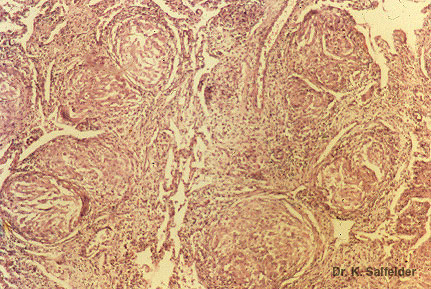

Abb. 9,33: Histoplasmose

Bei chronischen Infektionen sind Pilze in den Granulomen oft nur schwer zu lokalisieren. HE.-Faerbung